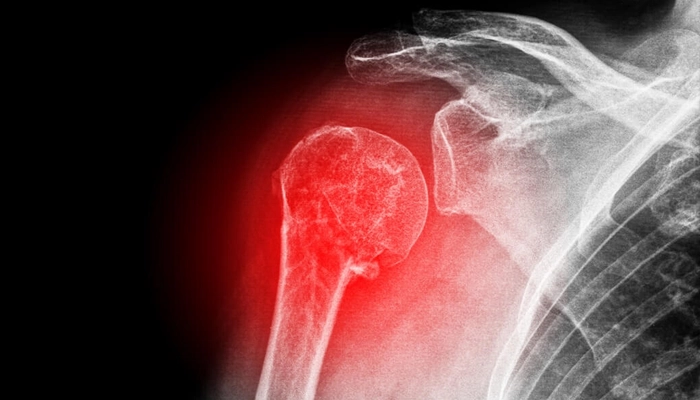

1. Sai khớp là gì?

Sai khớp (Dislocation) không đơn thuần chỉ là sự xê dịch của xương. Khi một khớp bị trật, các cấu trúc hỗ trợ xung quanh như dây chằng, bao khớp, gân và thậm chí là mạch máu, thần kinh cũng có thể bị tổn thương nghiêm trọng.

Bất kỳ khớp nào trên cơ thể cũng có nguy cơ bị sai, nhưng phổ biến nhất là:

Khớp vai: Khớp có biên độ vận động lớn nhất nên dễ bị trật nhất.